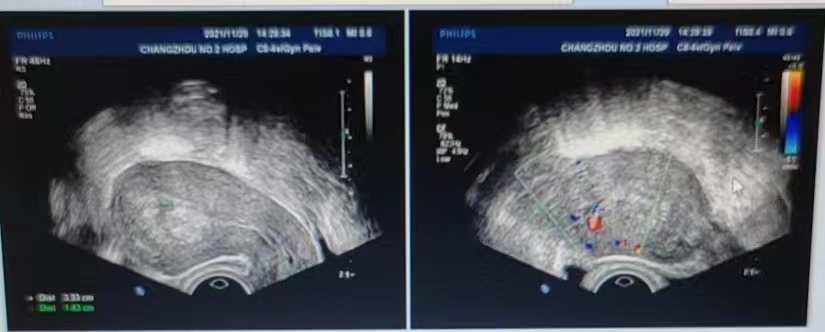

2022-02-21患者因停经1月余再次至我院就诊,查阴超提示宫内早孕,见胚芽1.5cm,可见心管搏动(图3),查血HCG>15000mIU/mL,建议其建卡定期产检,随访定期产检未见胎儿异常。后顺产一健康男婴。

图3:停药后早孕超声图